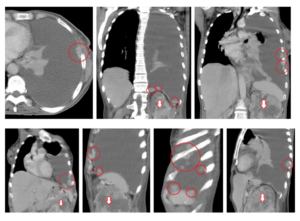

Компьютерную томографию легких (МРТ, ПЭТ) применяют для уточнения локализации и распространенности рака плевры, обнаружения инфильтрации грудной клетки, поражения легкого, медиастинальных лимфоузлов, перикарда, противоположного легкого.

- Компьютерная томография дает хорошую картинку, на которой прекрасно видна опухоль, ее размер и форма. Также можно оценить состояние соседних органов и тканей.

Компьютерная томография назначается для более детальной оценки мезотелиомы. С помощью КТ уточняется степень распространенности рака. Эту процедуру дополняет МРТ, посредством которого удается выявить наличие метастаз в соседние ткани и органы.